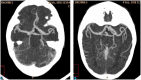

Results: In an 8-year-old boy presenting with severe aortic dilatation, facial dysmorphism, and overgrowth at birth a de novo p.Gly375Arg KCNMA1 mutation was identified which has been reported previously in association with gingival hypertrophy, aortic dilatation, and developmental delay. Additionally, in a 30-week-old fetus with severe growth retardation and duodenal atresia a de novo p.Pro805Leu KCNMA1 mutation was identified. The latter has also been reported before in a boy with severe neurological manifestations, including speech delay, developmental delay, and cerebellar dysfunction.

Conclusion: The current report presents the first antenatal presentation of a pathogenic KCNMA1 mutation and confirms the specific association of the p.Gly375Arg variant with early onset aortic root dilatation, gingival hypertrophy, and neonatal overgrowth.